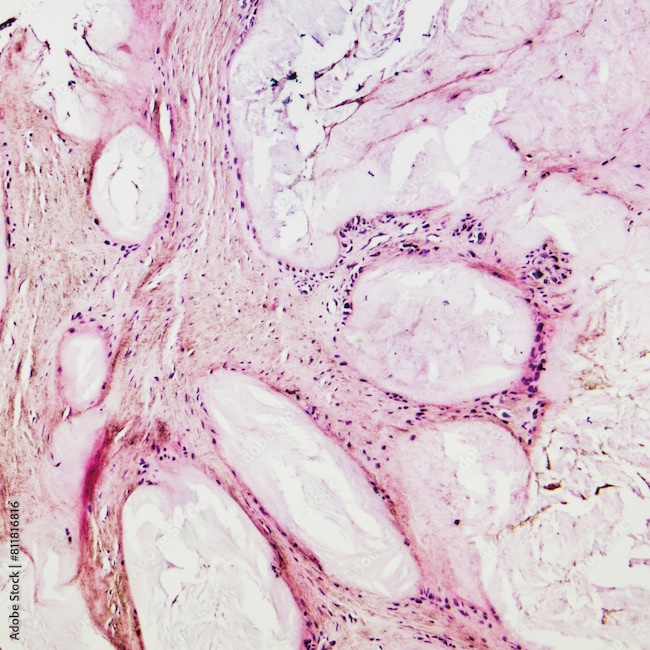

Connue sous le nom de syndrome de Churg-Strauss, la maladie fut en 2012 rebaptisée en granulomatose éosinophilique avec polyangéite (GEPA). Elle se définit comme une forme rare de vascularite nécrosante des moyens et petits vaisseaux, caractérisée par un asthme tardif et une hyperéosinophilie sanguine et tissulaire et classée parmi les vascularites à ANCA. Le fait que la GEPA partage des similitudes pathophysiologiques avec l'asthme à éosinophiles a mené à des développements thérapeutiques qui s'ajoutent au traitement standard par glucocorticoïdes et immunosuppresseurs. Une pathologie revisitée par le Pr Florence Roufosse (Hôpital Universitaire de Bruxelles - Hôpital Erasme).

La GEPA est la plus rare des vascularites associées aux anticorps anti-cytoplasme des polynucléaires neutrophiles (ANCA) avec une prévalence estimée à 1,5/100.000 personnes en Europe et un pic d'incidence entre 30 ans et 50 ans. L'étiologie semble auto-immune mais des facteurs génétiques de susceptibilité, des agents environnementaux, des agents infectieux joueraient aussi un rôle. La GEPA se développe en 3 phases, une phase prodromique marquée par un asthme avec ou sans rhinite allergique, une phase marquée par une hyperéosinophilie sanguine et une infiltration des tissus par les éosinophiles évoquant une éosinophilie pulmonaire simple, une pneumonie ou une gastroentérite à éosinophiles et une phase marquée par une vascularite avec ses manifestations systémiques. Les atteintes peuvent être notamment respiratoires avec un asthme (95% à 100% des patients) souvent sévère et corticodépendant, neurologiques (multinévrites, épilepsies...), musculosquelettiques (arthralgie, myalgie), cardiaques (insuffisance cardiaque, péricardite...), gastro-intestinales (douleurs abdominales, diarrhées...), rénales (glomérulonéphrites...) etc.